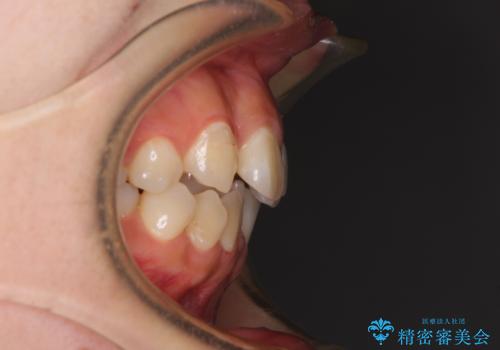

上顎の左右側切歯(前から2番目)が裏側に隠れいてる状態で、咬み合わせや清掃性に大きな問題が認められました。

左下に八重歯があったそうですが、当時は矯正治療を行うことを考えていなかったため、抜歯してしまったとのことでした。

叢生が著しいため、左下以外の第一小臼歯3本を抜去し、目立たないワイヤー装置にて矯正治療を行うこととしました。